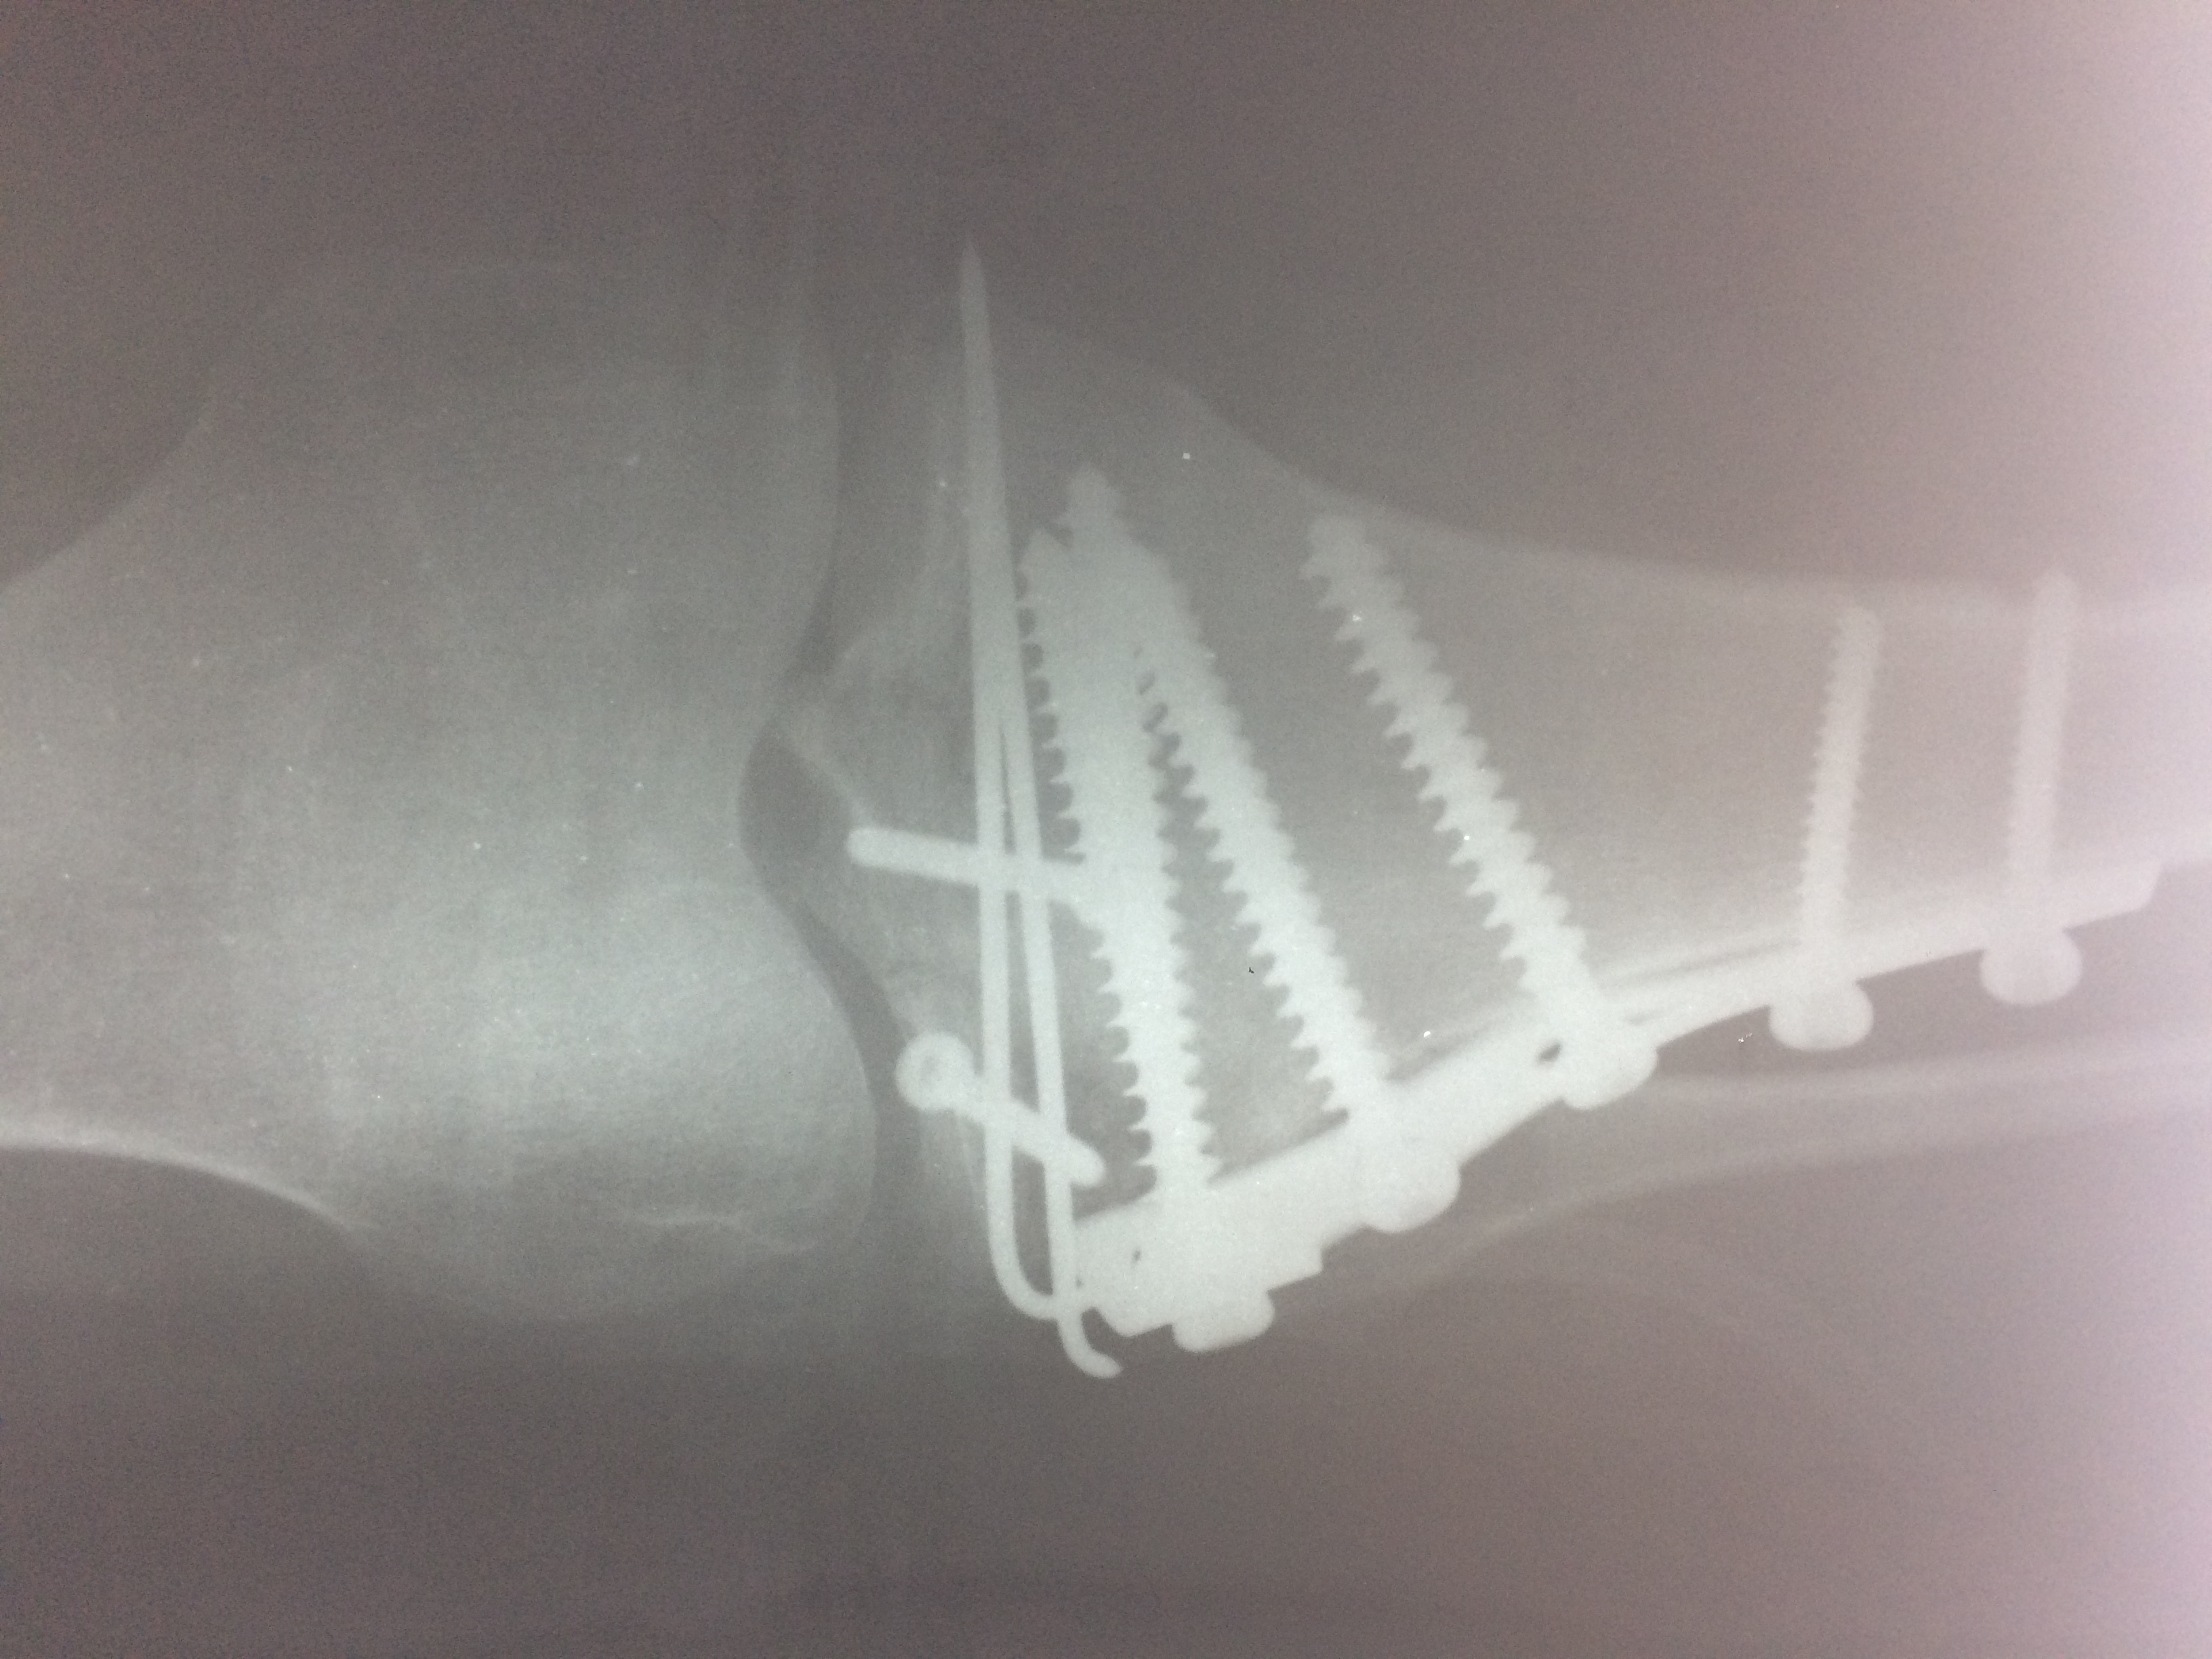

Операция - открытая репозиция, остеосинтез большеберцовой кости опорной пластиной с костной ксенопластикой маетриалом "Остеоматрикс". На контрольных снимках в три и шесть месяцев имеется консолидация перелома, миграции фиксатора нет, имеется остеоинтеграция ксенопластического материала. Функция коленного сустава полная.

Отдаленные результаты через 3 (три) месяца